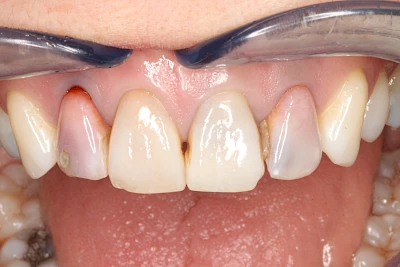

Dunkle bzw. Rötliche Verfärbung

Ist ein einzelner Zahn deutlich dunkler als die Nachbarzähne kann das ein Zeichen sein, dass der Nerv abgestorben ist. Unter Umständen wurde bereits eine Wurzelkanalbehandlung vom Zahnarzt durchgeführt. Eine Abklärung durch den Zahnarzt ist in jedem Fall sinnvoll.